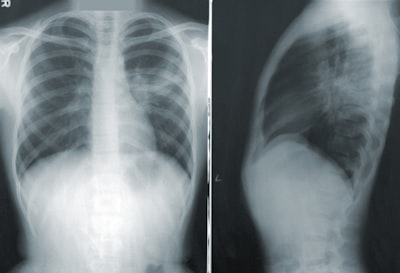

The company provides various imaging services, including ultrasounds, MRIs, CT scans, X-rays, and 3D mammograms, with Northwest Radiologists physicians interpreting the images.